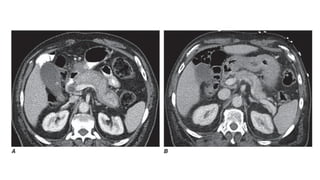

A. Contrast-enhanced CT scan of the abdomen demonstrates diffuse

pancreatic enlargement and a hypoechoic rim (capsule sign) in a

patient who presented with jaundice. The serum IgG4 level was

elevated to 942 mg/dL (reference range 4–86 mg/dL), so the patient

was diagnosed with definitive type 1 autoimmune pancreatitis.

B. Contrast-enhanced CT scan of the abdomen following a treatment

course with high-dose steroids demonstrates return to normal size of

the pancreas, reappearance of normal lobulations along the margin,

and absence of the hypoechoic rim.

A. Contrast-enhanced CTscan of the abdomen demonstrates diffuse pancreatic enlargement and a hypoechoic rim (capsule sign) in a patient who presented with jaundice. The serum IgG4 level was elevated to 942 mg/dL (reference range 4–86 mg/dL), so the patient was diagnosed with definitive type 1 autoimmune pancreatitis. B. Contrast-enhanced CT scan of the abdomen following a treatment course with high-dose steroids demonstrates return to normal size of the pancreas, reappearance of normal lobulations along the margin, and absence of the hypoechoic rim.